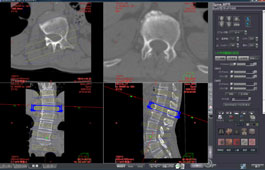

ADVANCED MPR BATCH

With this protocol a user can designate a pathway defining the acquisition of a sequential series of MPR images, with special applicability to spinal imaging.